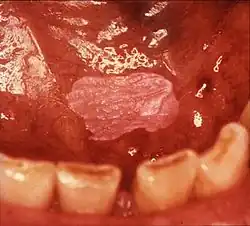

Non-homogeneous leukoplakia

Non-homogeneous leukoplakia is a lesion of non-uniform appearance. The color may be predominantly white or a mixed white and red. The surface texture is irregular compared to homogeneous leukoplakia, and may be flat (papular), nodular or exophytic.[9][15] "Verrucous leukoplakia" (or "verruciform leukoplakia") is a descriptive term used for thick, white, papillary lesions. Verrucous leukoplakias are usually heavily keratinized and are often seen in elderly people. Some verrucous leukoplakias may have an exophytic growth pattern,[2] and some may slowly invade surrounding mucosa, when the term proliferative verrucous leukoplakia may be used. Non-homogeneous leukoplakias have a greater risk of cancerous changes than homogeneous leukoplakias.[9]